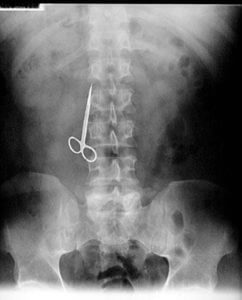

“I’ve taken cocaine out of rectums, I’ve taken cocaine out of vaginas… I’ve seen everything, and everything I’ve seen!”